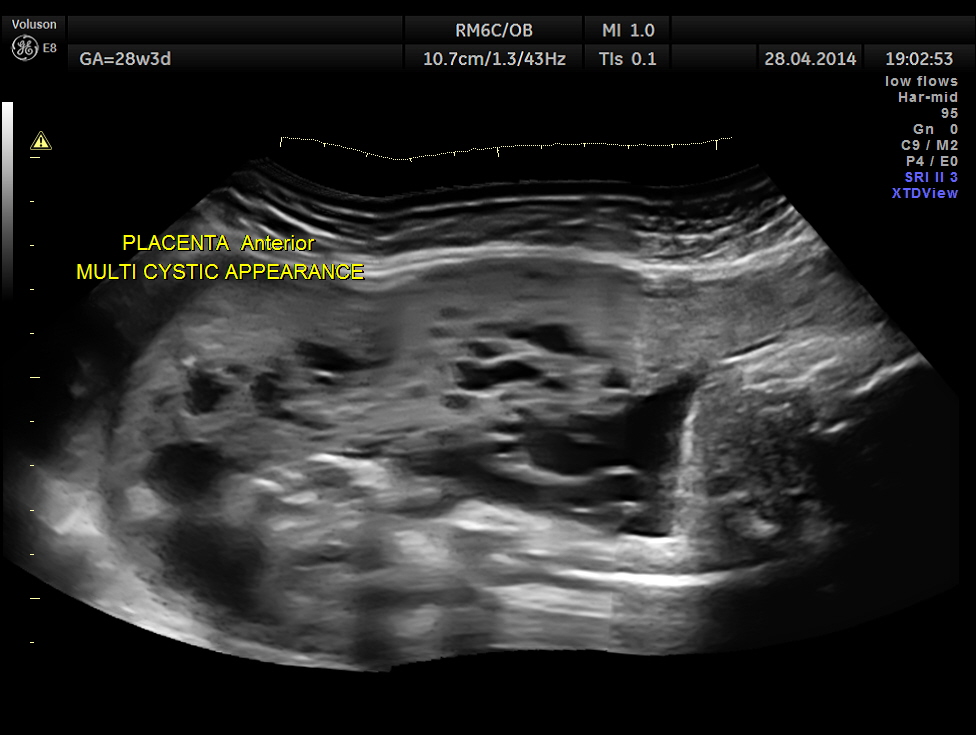

The placenta was on the anterior wall and the scan showed a distinct mass lesion in the antero right lateral portion. The placenta had multiple small cystic appearance in the right lateral aspect . Colour doppler showed no increased vascularity.

In the earlier report , it was suggested as a possible partial vesicular mole or a placental dysplasia. After reviewing the 1st trimester scan report , I felt that vesicular mole was unlikely as it could not have appeared after 14 weeks and gave a diagnosis of PLACENTAL DYSPLASIA with advise for periodic follow up. The patient wanted another opinion and went to the referral centre at Chennai , where they had again given the differential diagnosis of partial vesicular mole or placental dysplasia.